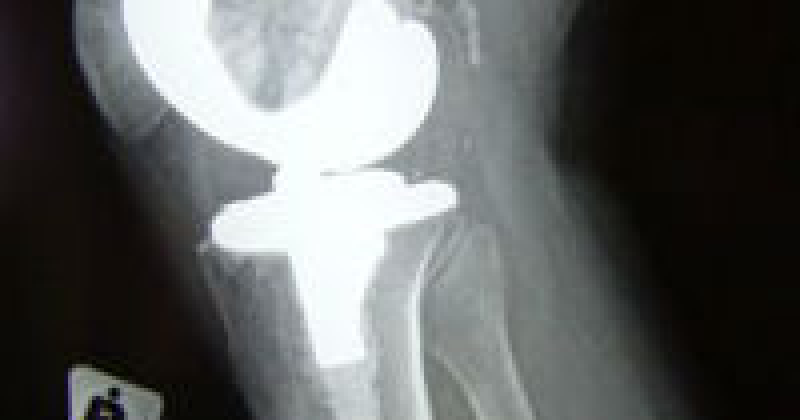

Articulatiile pot suferi procese inflamatorii (artrite) sau degenerative (artroze), al caror simptom dominant este durerea articulara.